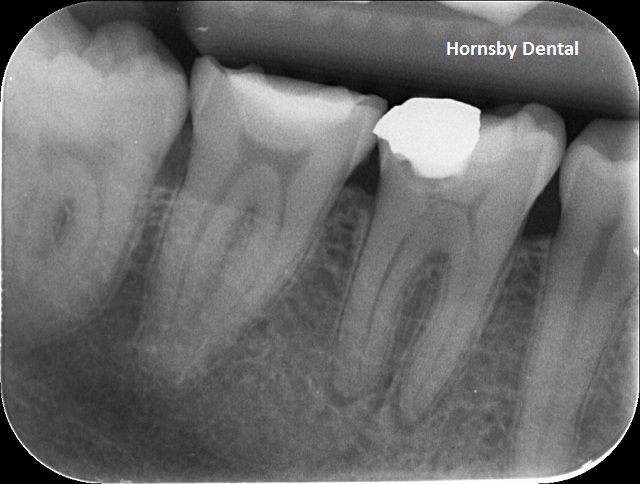

PRE-OP

Pre-op: Deep decay underneath old restoration. Previously un-monitored and the tooth was in excruciating pain. Large shadow underneath the opaque white mass is the decay, and at tip of the tooth root is a dark shadow which suggests a zone of infection. The tooth can be saved with a carefully performed root canal therapy and avoid the loss of the tooth